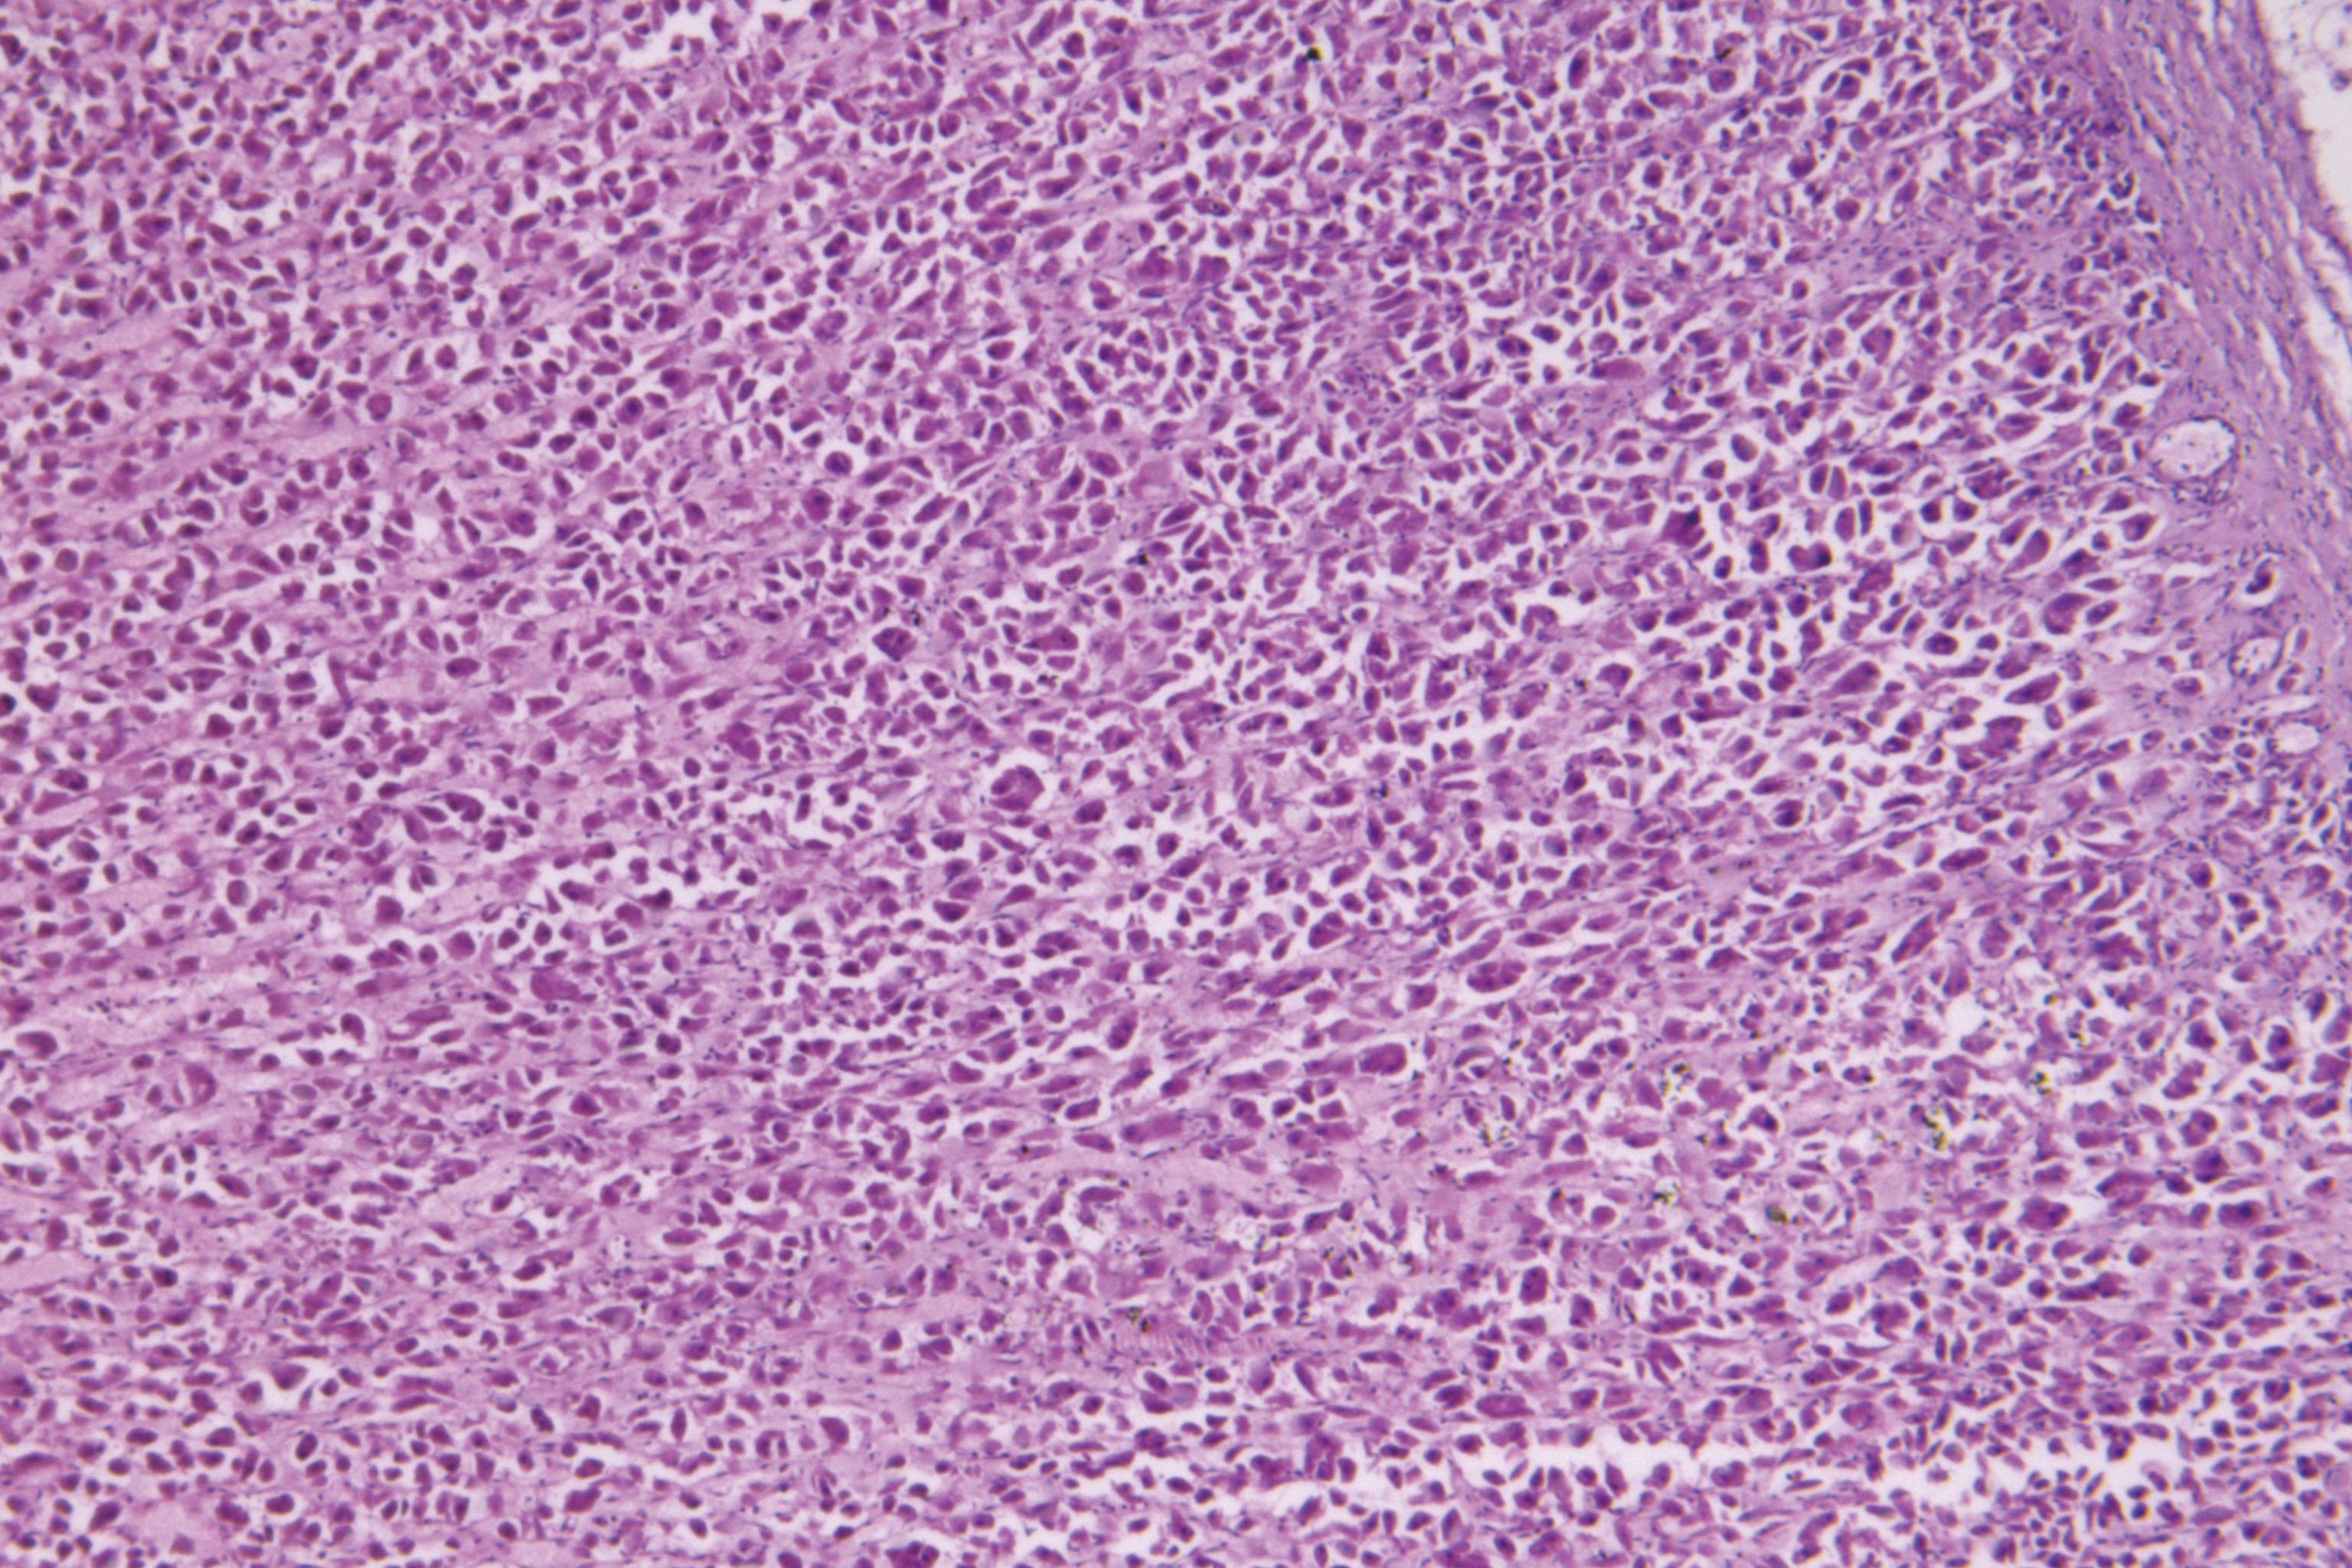

| [3] | 陈轩龙, 袁强, 孙勇, 张碟, 伏建斌, 李立亮. 米酵菌酸中毒后死亡法医学鉴定1例[J]. 法医学杂志, 2025, 41(3): 277-280. |

| [5] | 陈轩龙, 袁强, 孙勇, 张碟, 伏建斌, 李立亮. 米酵菌酸中毒的法医学研究进展[J]. 法医学杂志, 2025, 41(2): 111-119. |

| [14] | 杨辉煌, 刘霞, 王振, 石瑞, 史为博, 张国忠, 毕海涛, 李英敏. 敌草快中毒后延迟性死亡法医学鉴定1例[J]. 法医学杂志, 2025, 41(2): 181-184. |